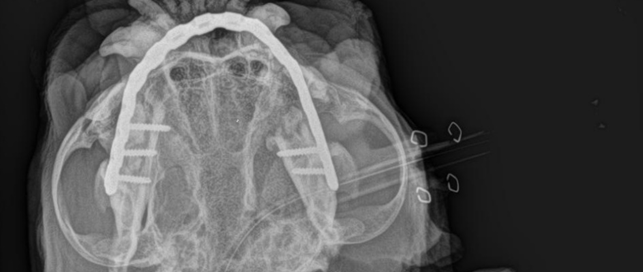

Stérilisation par cœlioscopie chez les chiennes atteintes de la maladie de von Willebrand

Histoire de Caladrius Rédigé par: Dr. Constance ORBAN et Dr. [...]